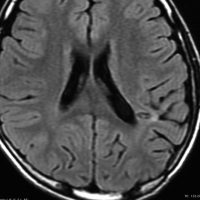

10歳でてんかん発症して難治性になった例

まだ日本にMRIが普及してなかった1988年,10歳でてんかん発作を発症しました。当時は,DNTという病名自体も知られていませんでした。これも典型的なDNTのMRI画像です。20代後半になって,複数の抗てんかん薬で治療を受けていましたが,難治性の発作をしばしば生じていました。発症してすぐに腫瘍摘出をしたほうがよかったのかもしれません。